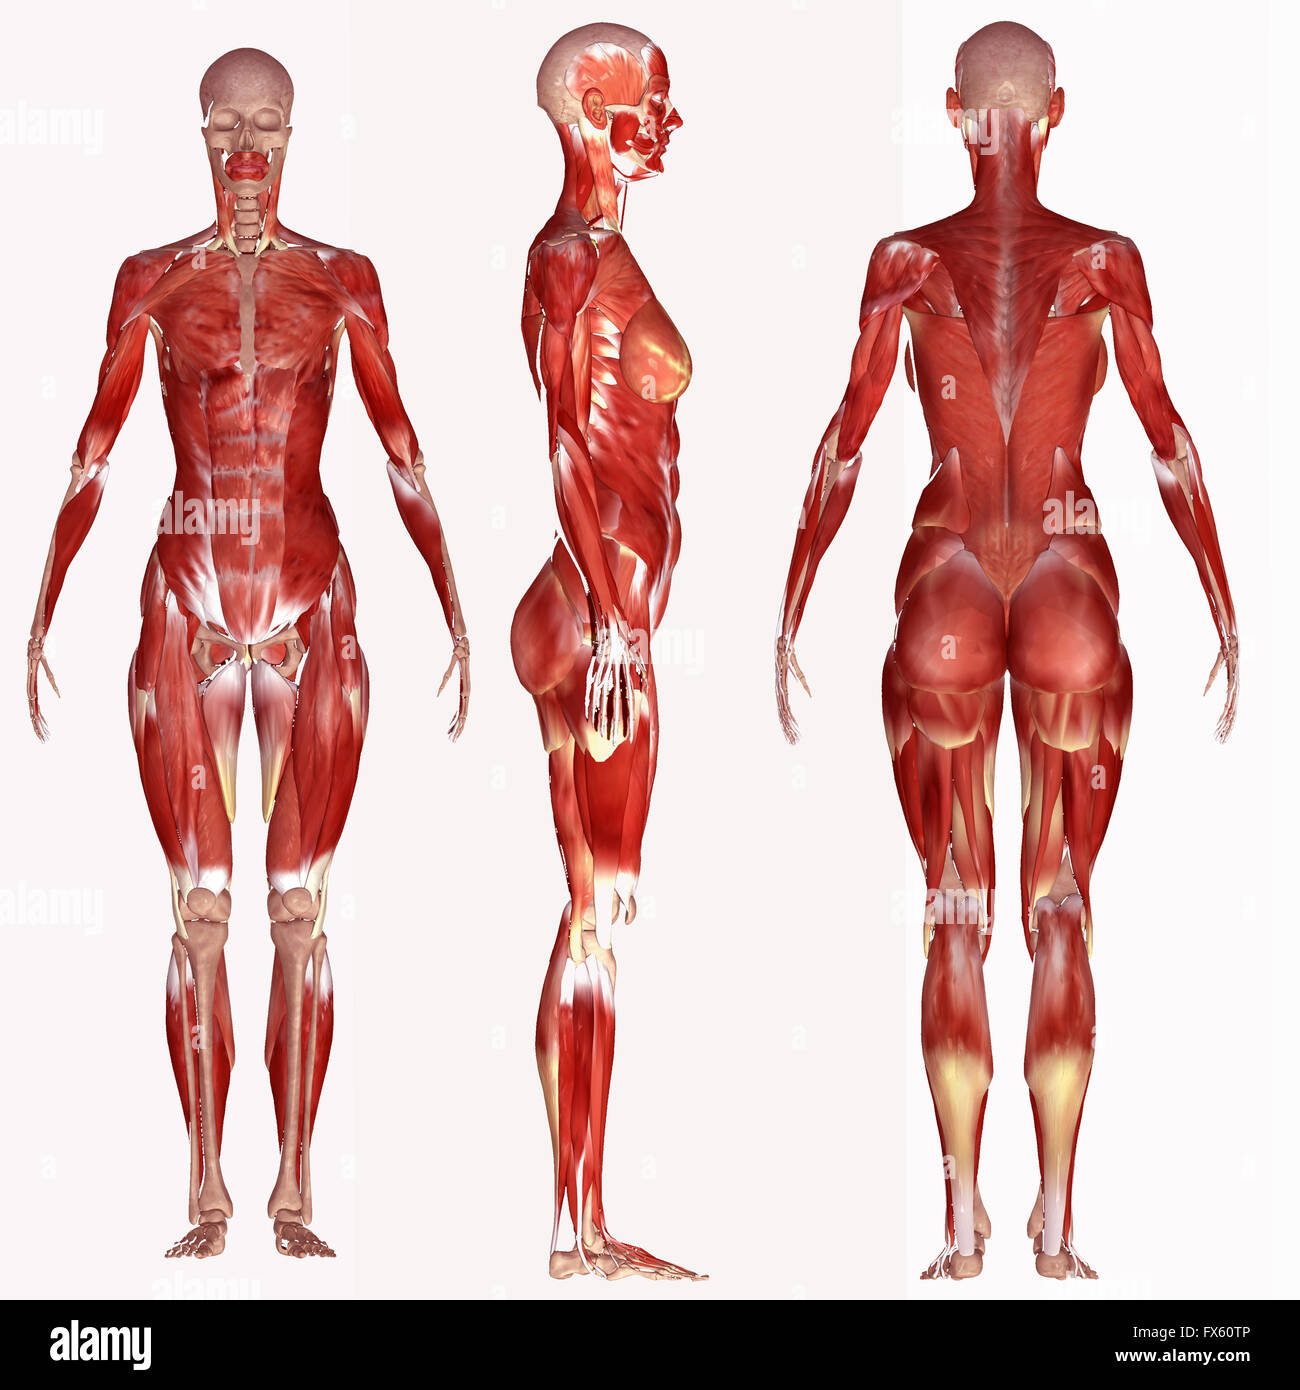

RMFX60TP–Menschen, Anatomie, Muskel, Körper, medizinische, Medizin, Illustration, Mann, Männlich, Gesundheit, muskulös, Wissenschaft, System, Biologie, Muskeln, ich